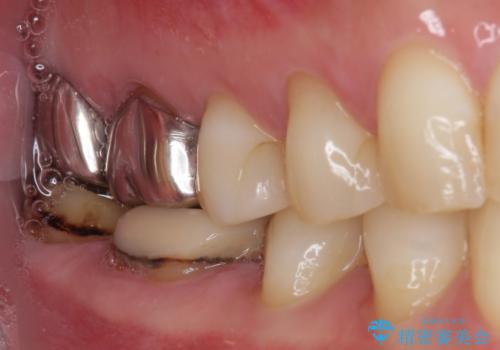

- 以前、職場近くで夜遅くまで治療していた医院で装着した奥歯のクラウンが、壊れたり汚れたりしていることを気にして来院された患者様です。

以前は安価であったことからハイブリッドクラウンを選択されたそうですが、すぐに具合が悪くなってしまったので、今回はオールセラミッククラウンにて補綴治療を行うこととしました。

咬合力が強く、土台の歯の高さが低かったたため、より高強度のフルジルコニアクラウンにて補綴治療を行いました。